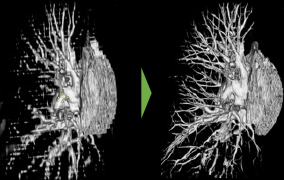

富士フイルム 医療分野における画像処理技術 (一部例)